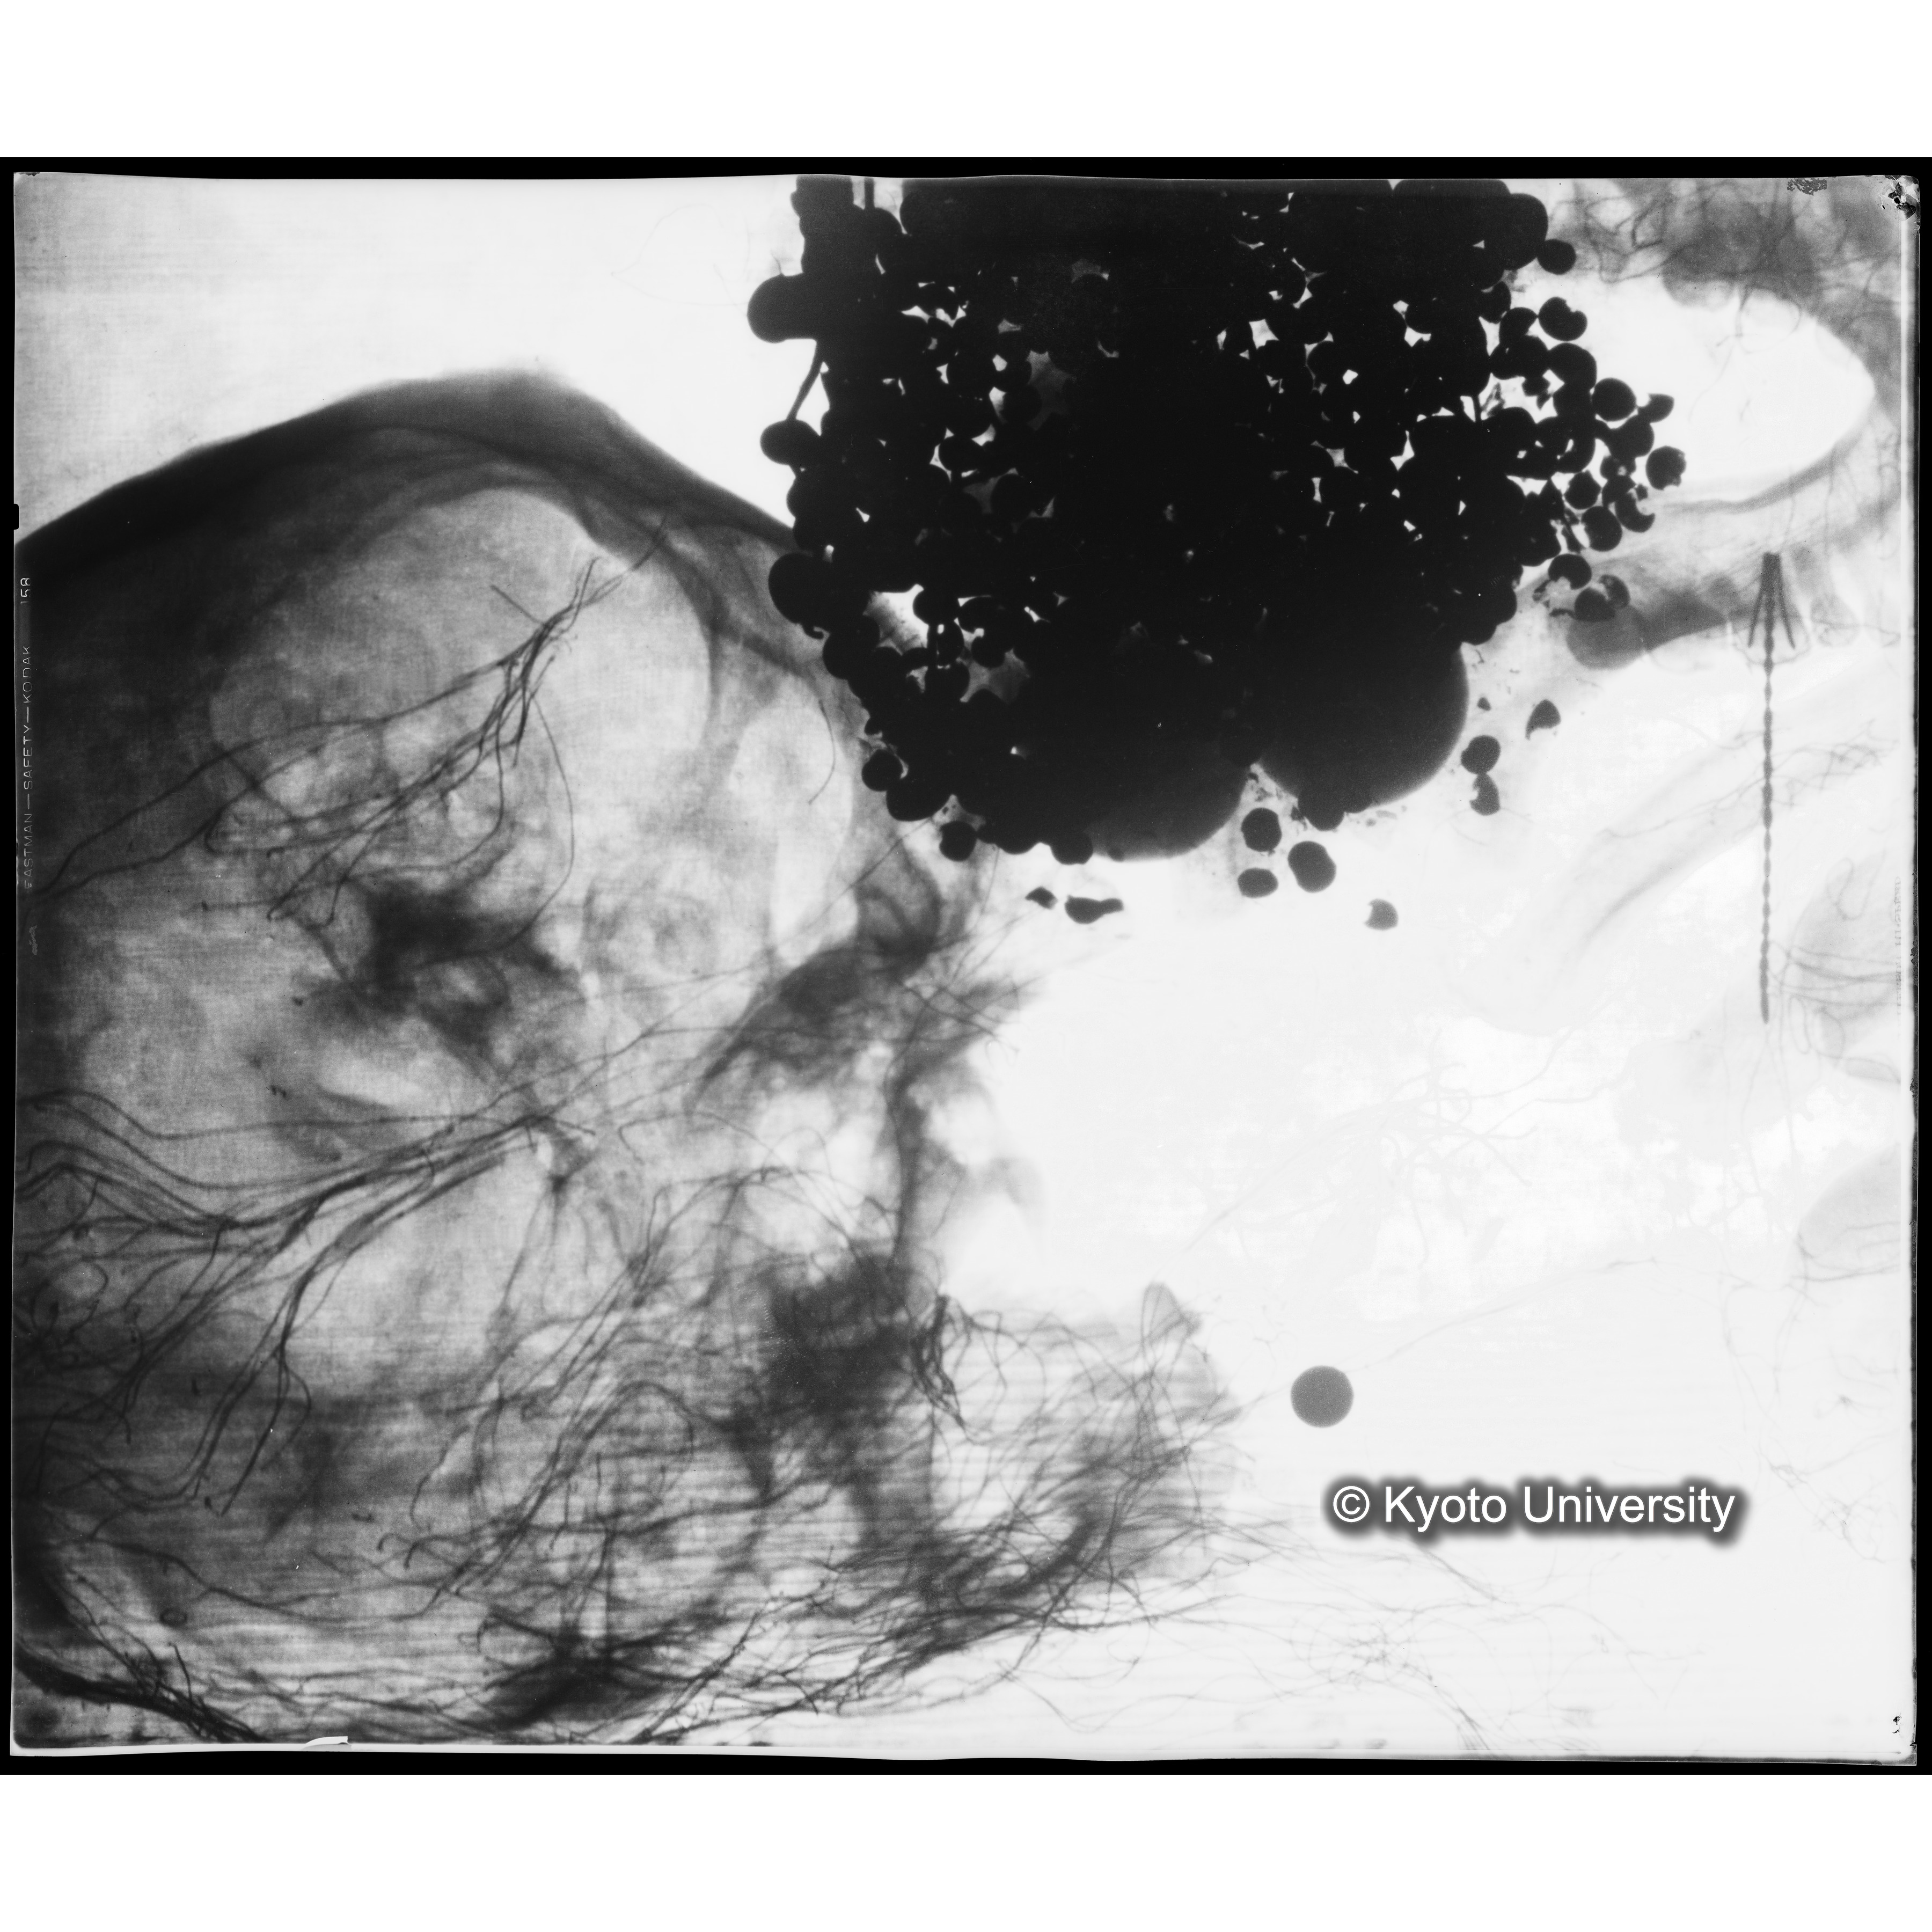

[写真内容] 頭部レントゲン2